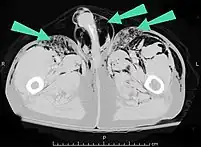

Air can be trapped under the skin in necrotizing infections such as gangrene, occurring as a late sign in gas gangrene,[2] of which it is the hallmark sign. Subcutaneous emphysema is also considered a hallmark of fournier gangrene.[26] Symptoms of subcutaneous emphysema can result when infectious organisms produce gas by fermentation. When emphysema occurs due to infection, signs that the infection is systemic, i.e. that it has spread beyond the initial location, are also present.[9][21]